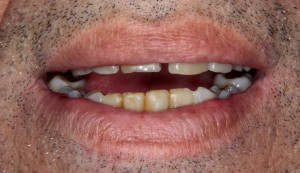

На верхней фотографии — почти начало лечения: месяц назад мы вынуждены были удалить нижние резцы, параллельно начали ортодонтическое лечение на верхней челюсти.

Исходная ситуация: пациенту чуть больше 60 лет, тяжелый пародонтит, вызванный проблемами с прикусом. В последнее время отмечает, что после потери зубов на верхней челюсти, оставшиеся зубы «поехали» в разные стороны. Был на консультации в другой клинике, где предложили удалить все зубы на верхней челюсти и изготовить съемный протез — пародонтит же!

Месяц назад мы удалили пациенту сильно подвижные нижние резцы (по данным компьютерной томографии стало ясно, что их не спасти), а наш ортодонт Яна Акопян приступила к ортодонтическому лечению, цель которого — устранить большие межзубные промежутки и восстановить нормальное функциональное соотношение зубов верхней и нижней челюстей.

Кстати, данный случай — хороший пример ортодонтического лечения у пациентов взрослого и пожилого возрастов. Отлично разбивает миф о том, что исправление прикуса возможно только в детстве.